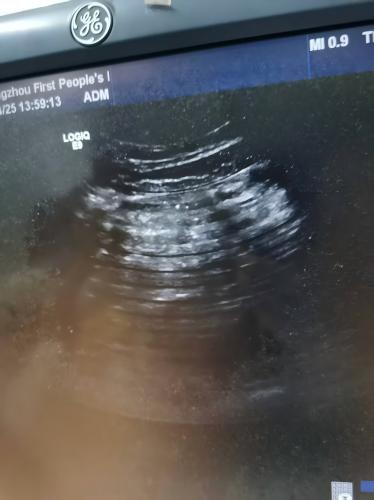

故障描述:GE LOGIQ E9彩超使用浅表探头做乳腺时出现明显分层情况,远场一片白色噪点看不清;腹部探头出现多圈暗条采集图像模糊。

GE LOGIQ E9彩超4387-1.jpgGE LOGIQ E9彩超4387-2.jpg